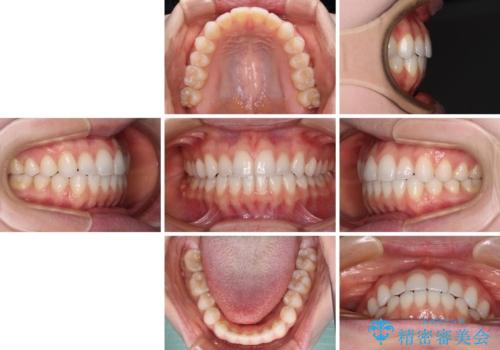

上下前歯が接触しない オープンバイトをインビザラインで改善

- 前歯の上下スペースによる食べにくさを気にして来院された患者様です。

インビザラインにより上下の前歯の隙間を閉じていくこととしました。

上下の奥歯を圧下させるようにすることで、前歯を接触させるように計画しました。

上下の隙間に舌が入り込むことがオープンバイトの原因であったため、舌の筋肉のトレーニングも並行して行い、後戻りの抑制を図りました。